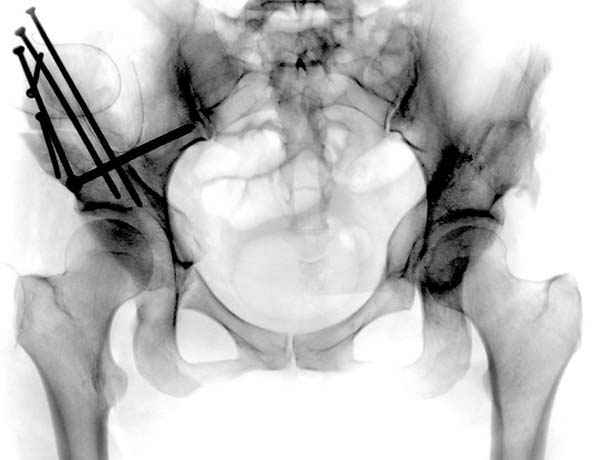

Но, занимаясь с этой патологией, собрал небольшой опыт в лечении остеоартрита, включая: периацетабулярную (ориентационно-корригирующую) остеотомию, и на проксимальной части бедра - valgus, varus, flexion and extension osteotomy и в комбинациях, базирующуюся на авангардных учениях Reinhold Ganz из Bern, на конгруентности сустава и увеличения контактной площади в суставе для уменьшения давления на площади хряща, При Вашем желании можно продемонстрировать результаты наших операций на слайдах.

Если Вам не трудно, не смогли бы Вы представить материал о том, в каких из перечисленных 1500 Ваших операций и 1500 ассистенциях, было применено Ваше открытие по коррекции тазобедренного сустава, потому что морфомеханика связана с варус или валгус остеотомиями на проксимальном отделе бедра.